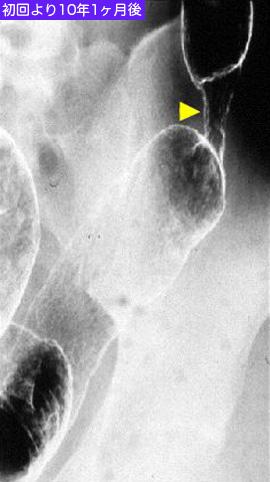

Caso Concurrente de PSC (Primary sclerosing cholangitis) y Cáncer de Colon, los cuales causaron la Colitis Ulcerosa

40-44

[Image-ID:9936]

colon/ascendente

método de exámen

Rayos X

40 -